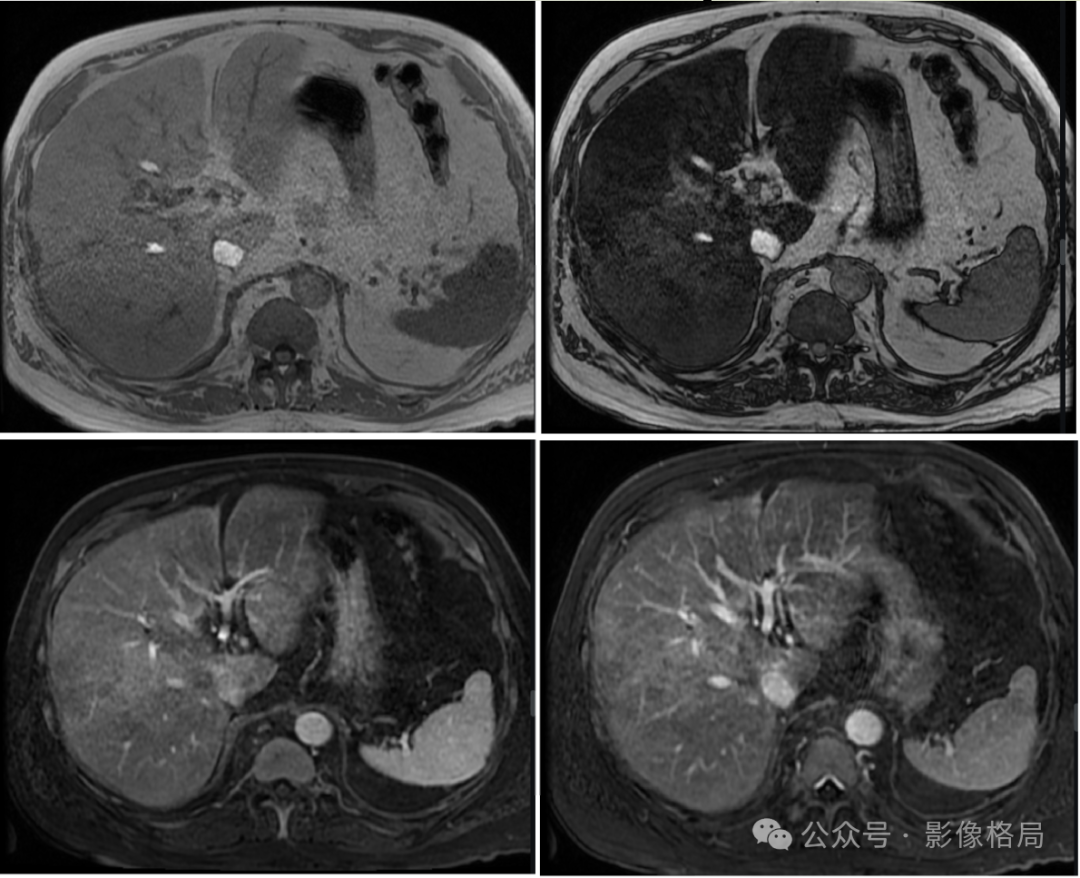

From left to right, top to bottom, are T1WI in-phase, T1WI out-of-phase, T1WI+C, and T1WI+C fat-suppressed.

The liver tissue shows diffuse signal reduction on out-of-phase, confirming nodular/map-like steatosis.